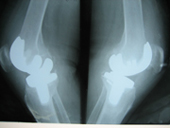

Arthriis of both hips pre op Arthriis of both hips post op Arthritis knee valgus deformity pre op Arthritis knee valgus deformity post op